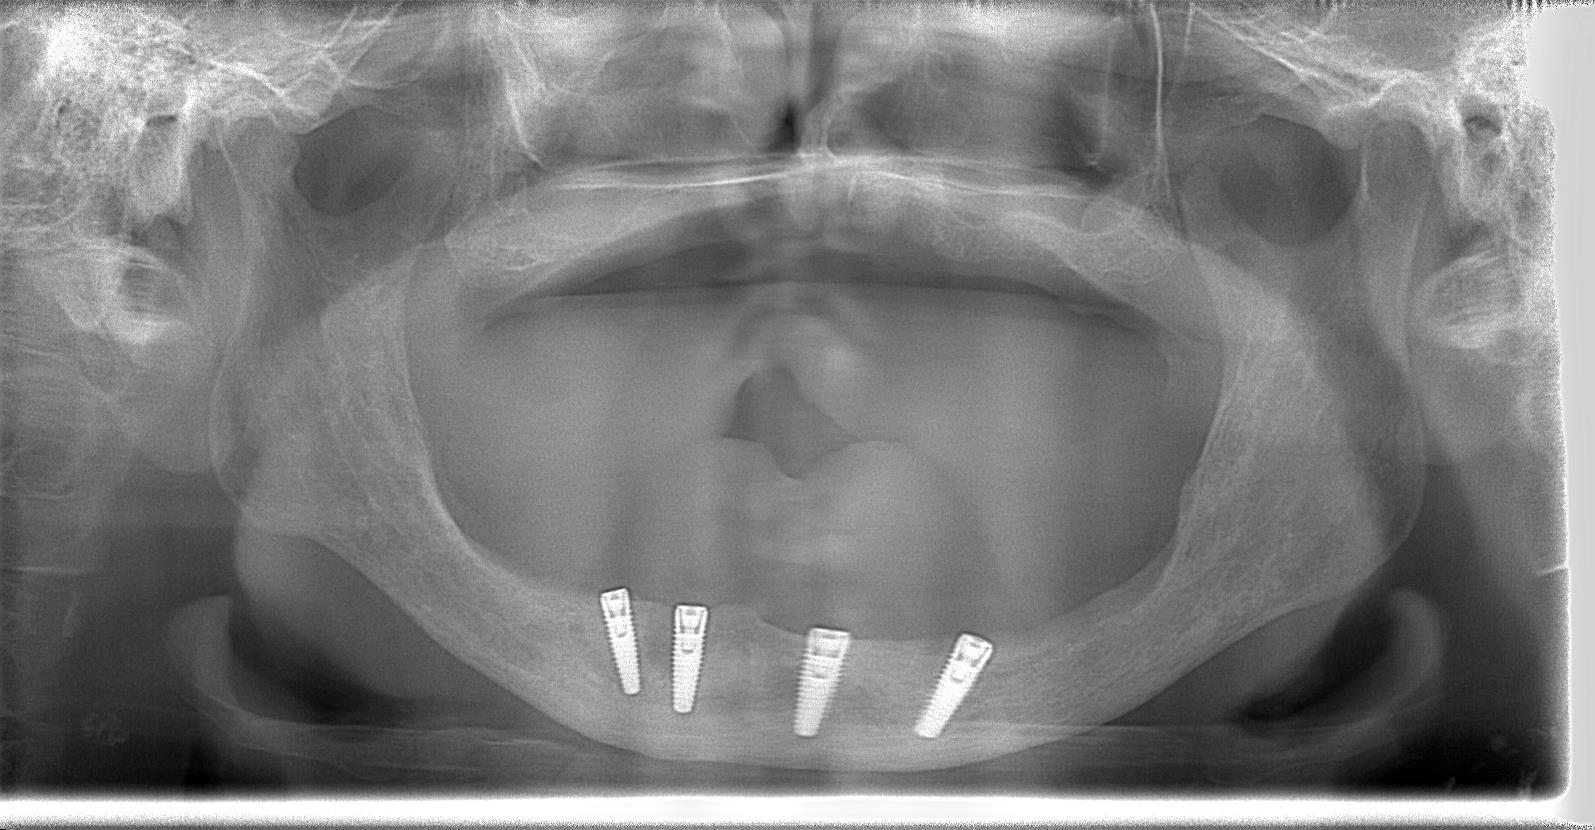

術後パノラマレントゲン写真